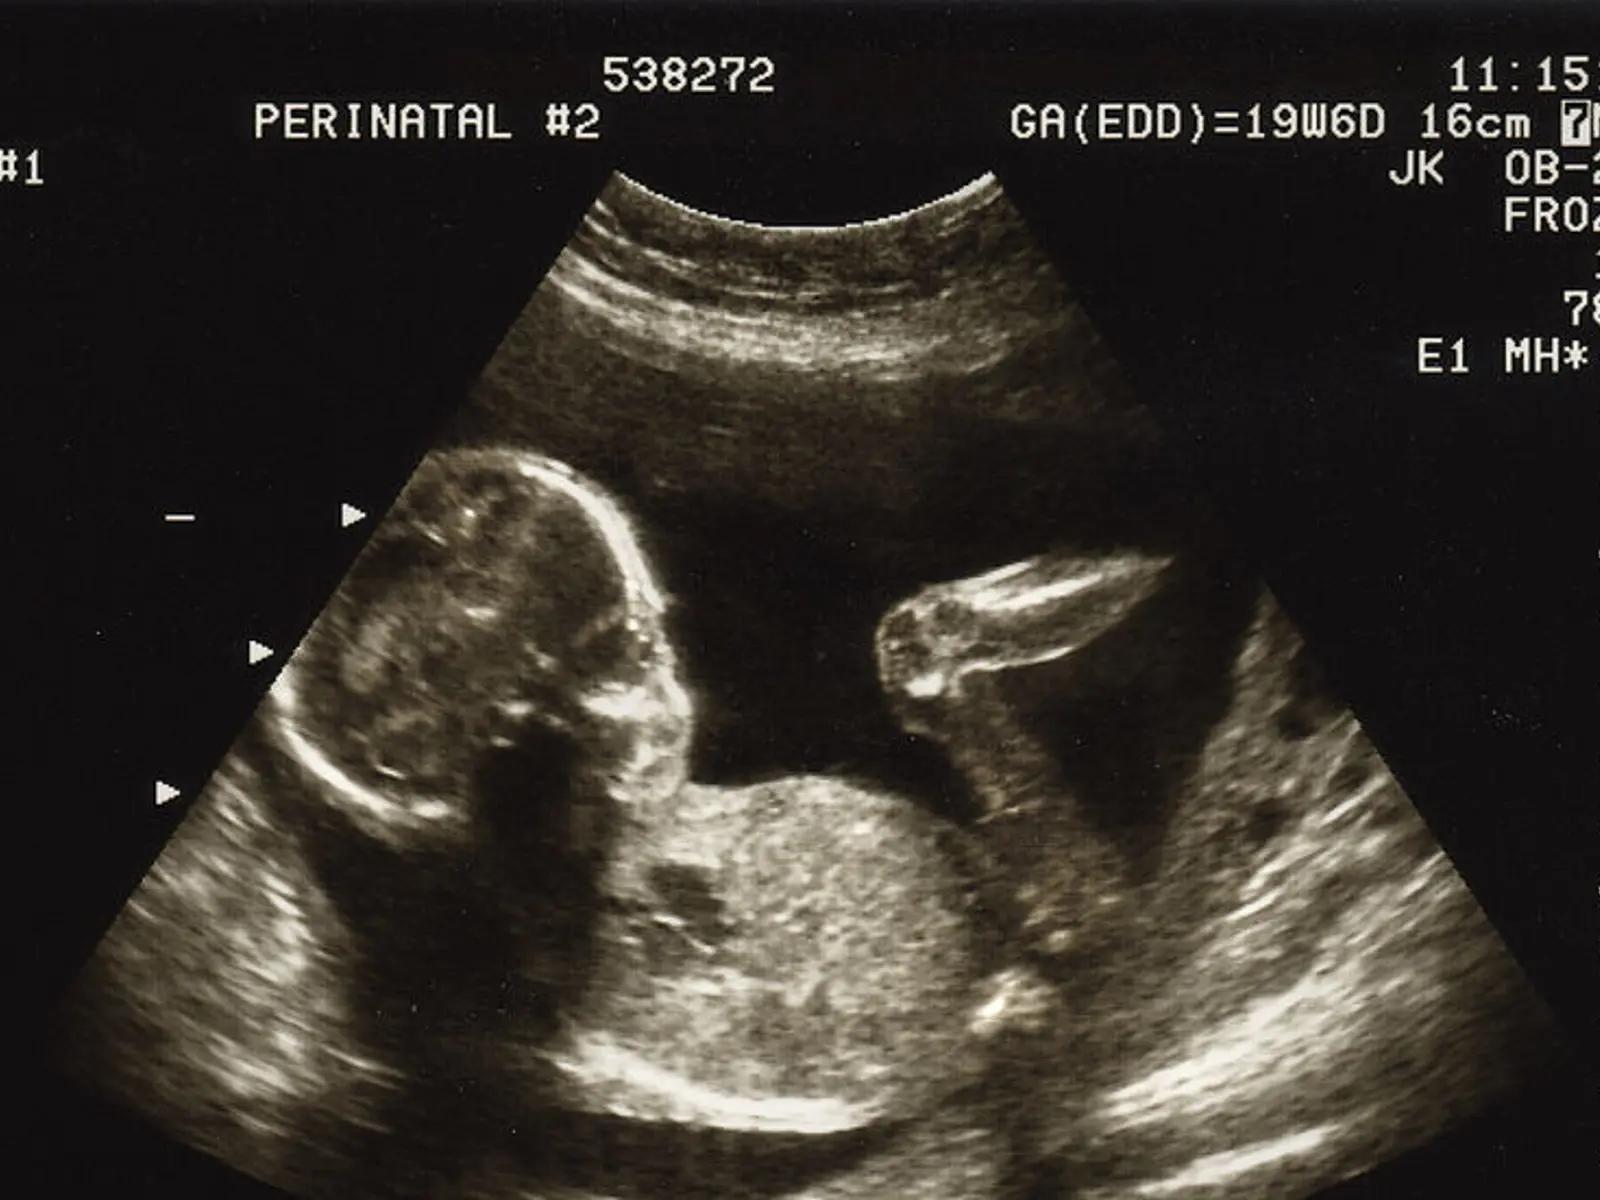

Die Nackenfaltenmessung wird im Rahmen eines Ultraschalluntersuchs durchgeführt. Der Arzt oder die Ärztin misst mit einem speziellen Gerät die Dicke der Nackenfalte des Fötus. Die Messung erfolgt in Millimetern und wird in einem Messprotokoll festgehalten. Die Nackenfalte ist eine Flüssigkeitansammlung im Nackenbereich des Fötus, die im ersten Trimester der Schwangerschaft normal vorhanden ist. Bei einem erhöhten Risiko für Chromosomenstörungen ist die Nackenfalte jedoch oft dicker als normal.